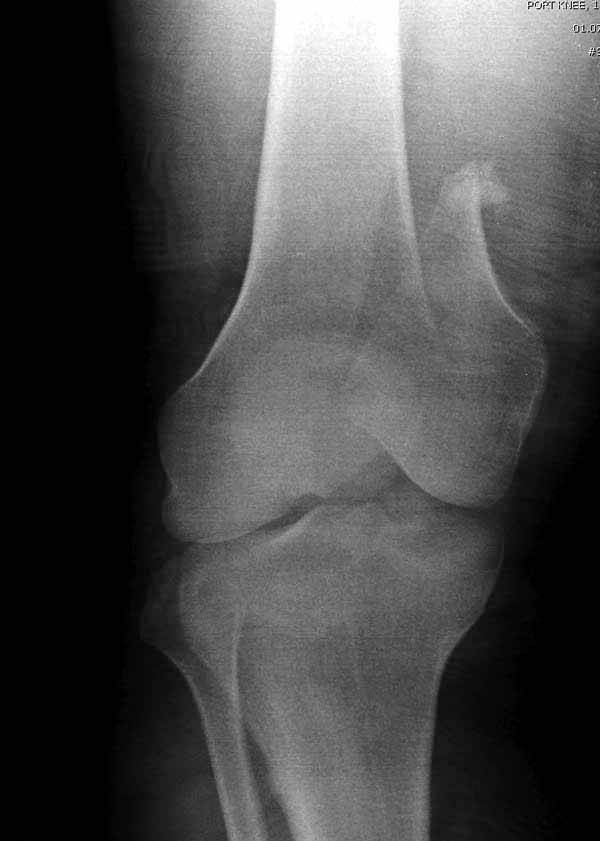

>Сразу не обратил ваше внимание именно на это, что сломаны оба мыщелка, и больший является именно медиальным мыщелком

А теперь по поводу лечения перелома. Среди всех чрез/меж-мыщелковых переломов в 38% сопровождются переломом в корональной плоскости, т.е перелом Hoffa. Nork et al, J Orthop Trauma, 87:564, 2005.

По снимку вроде одиночный простой мыщелковый перелом, и такой внутрисуставной перелом не обязательно дистрагировать на скелетном вытяжении, потому что не не нарушается непрерывность колонны с одной стороны. И для таких простых переломов подойдет любой метод: 95 градусная пластина, Lat. Condylar Butress пластина или ретроградный гвоздь. А для особых энтузиастов которые желают антеградную фиксацию, возможно легко найти трохантер у алкоголиков или дистрофиков. А вот у откормленных Макдональдскими гамбургерами? Если поискать у них тоже можно найти, но стоит ли?

У больных как в этом случае, с вовлечением двух мыщелков правильно, что сделали вытяжение до операции. Здесь имеется флексионный компонент на другой стороне, и я бы рекомендовал операцию делать из двух доступов. Сперва фиксировать медиальную колонну custom made пластиной, обычно 1/3 тубулярной пластиной в 4.5 мм, потому что пока производители опаздывают с медиальной пластиной.